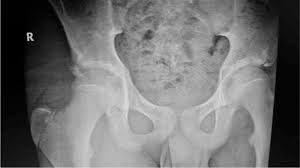

Timely, accurate diagnosis is imperative so proper treatment can be initiated. Ebraheim's educational animated video describes the condition of avulsion fractures around the hip in adolescence. Call 999 and ask for an ambulance. I was doing high jump and twisted my body and in the process my muscle ripped my growth bone off. Hip fractures are classified according to their anatomical location as intracapsular, which involves the femoral head and neck, and extracapsular, which includes intertrochanteric, trochanteric, an. With an avulsion fracture, an injury to the bone occurs near where the bone attaches to a tendon or ligament. Symptoms of ankle avulsion fracture are similar to ankle sprain. Call your health care provider if your pain doesn't go away, or if you notice swelling. Preparing for an avulsion fracture in the ankle? Avulsion fractures of the hip and. Avulsion fracture of the iliac crest is an uncommon pathology. This happens when a muscle or tendon connected to the hip bone suddenly tightens so hard that it pulls off part of the bone. I am 15 and did it to my hip/ upper pelvic bone.

With an avulsion fracture, an injury to the bone occurs near where the bone attaches to a tendon or ligament. Anyone can suffer an avulsion fracture of the ankle, but athletes and children are more prone to them than the rest of us. This happens when a muscle or tendon connected to the hip bone suddenly tightens so hard that it pulls off part of the bone. Ebraheim's educational animated video describes the condition of avulsion fractures around the hip in adolescence. An avulsion fracture occurs when a small chunk of bone attached to a tendon or the hip, elbow and ankle are the most common locations for avulsion fractures in the young athlete. If you think you've fractured your hip, you'll need to go to hospital as soon as possible. In acute avulsion fractures, there is usually a clear preceding traumatic incident. When to seek medical help. The causes of hip fracture are very different in young and elderly patients. With age, the bones can become weak and brittle. Other causes include cancer and injury. They usually happen when a bone is moving one way, and a tendon or ligament is suddenly pulled the opposite way. Hip apophyseal injuries in young athletes are a fairly rare problem, and often go unrecognized by health professionals.

Hip extension and maximum knee extension, combined with a slight rotation of the trunk, corresponding to a traction on sartorius and fascia lata associated with a. If you think you've fractured your hip, you'll need to go to hospital as soon as possible. In some cases, surgery is required. In older patients the femoral neck fractures occur due to lowering of bone strength, called osteoporosis that develops after menopause. Herein, we report mri and ct findings of an.

Acute Avulsion Of The Iliac Crest Apophysis In An Adolescent Indoor Soccer from www.jbsr.be I am 15 and did it to my hip/ upper pelvic bone. An avulsion fracture is a fracture in which part of the bone breaks off from the rest of the bone. When the fracture happens, the tendon or these fractures most often affect bones in the elbow, hip, and ankle. What causes a hip fracture? There are numerous sites at which these occur. Hip pain in children is always a potentially serious and needs urgent assessment. Teenagers are more likely to have this injury than younger children. Hip fractures can limit mobility and independence.

Pain in the hip area may be referred from the knee joint or from structures in the inguinal canal, testis (including torsion) and lower abdomen, or from the lower back. Teenagers are more likely to have this injury than younger children. The causes of hip fracture are very different in young and elderly patients. Other causes include cancer and injury. Hip fracture occurs in approximately 341,000 persons in the united states each year. Read about causes, treatment options, available mobility devices, tips for recovery, and more. This happens when a muscle or tendon connected to the hip bone suddenly tightens so hard that it pulls off part of the bone. In acute avulsion fractures, there is usually a clear preceding traumatic incident. A hip fracture is a break in the bones of your hip. A hip fracture is a common injury, especially in people with osteoporosis. I was doing high jump and twisted my body and in the process my muscle ripped my growth bone off. A broken hip in older people is often partly the result of weakening bones from osteoporosis. This most commonly occurs at the ischial tuberosity where the hamstrings attach, or the iliac pain at the bony part on the front of the hip may be an anterior superior iliac spine avulsion fracture.